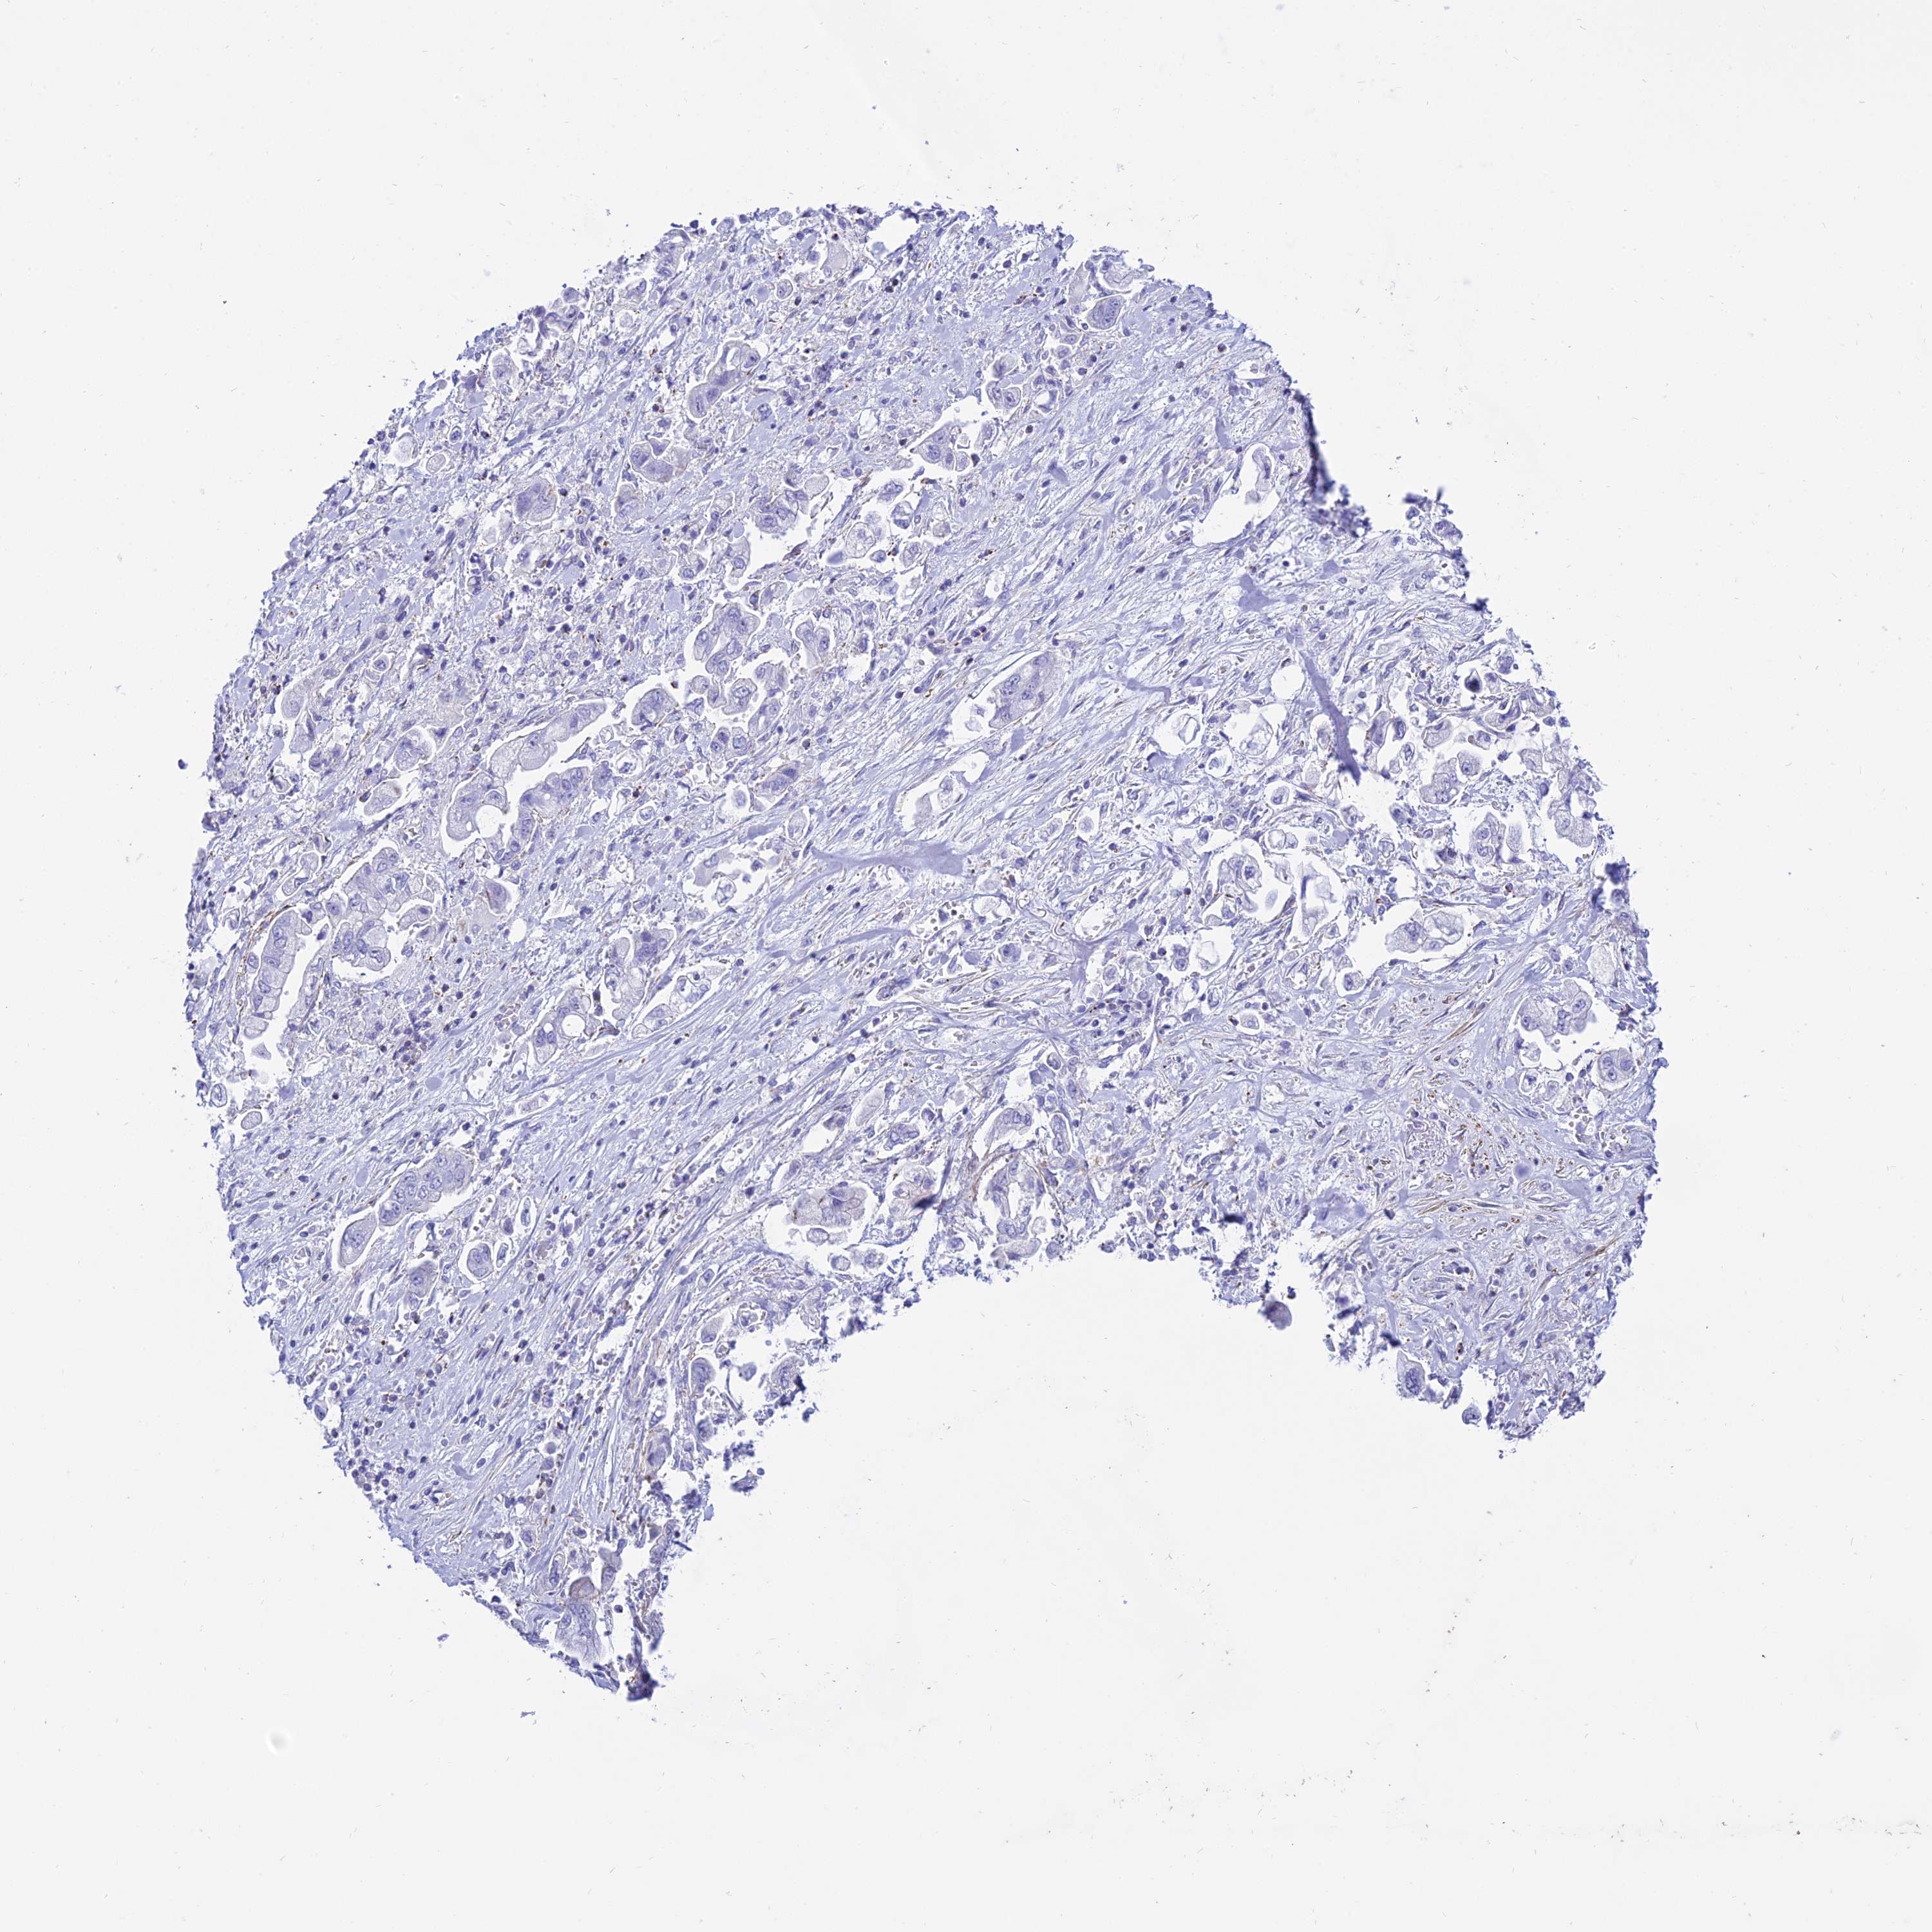

STOMACH CANCER - Protein expressioni

A mouse-over function shows sample information and annotation data. Click on an image to view it in a full screen mode. Samples can be filtered based on level of antibody staining by selecting one or several of the following categories: high, medium, low and not detected. The assay and annotation is described here.

Note that samples used for immunohistochemistry by the Human Protein Atlas do not correspond to samples in the TCGA dataset.

Antibody stainingi

Antibody staining in the annotated cell types in the current human tissue is reported as not detected, low, medium, or high, based on conventional immunohistochemistry profiling in selected tissues. This score is based on the combination of the staining intensity and fraction of stained cells.

Each image is clickable and will lead to virtual microscopy that enables deeper exploration of all samples and also displays staining intensity scores, fraction scores and subcellular localization as well as patient and tissue information for each sample.

Antibody HPA045884

Staining

High

Medium

Low

Not detected

Intensity

Strong

Moderate

Weak

Negative

Quantity

>75%

75%-25%

<25%

None

Location

Nuclear

Cytoplasmic/membranous

Cytoplasmic/membranous,nuclear

Adenocarcinoma, NOS